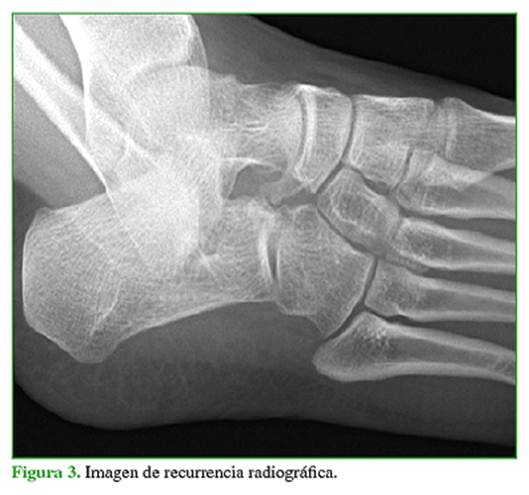

Previa anestesia general y profilaxis antibió́tica en la inducció́n anestésica, se coloca un manguito hemostá́tico en el muslo y se toman medidas de antisepsia. Se ubica al paciente en decúbito dorsal con un realce en la regió́n lateral del glúteo. Se realiza un abordaje lateral oblicuo de 3 a 4 cm centrado en la coalició́n. Se incide sobre la aponeurosis del músculo pedio. Se lo desinserta cuidadosamente de su origen proximal con electrobisturí y se lo jalona con Vicryl 0. Se identifican la coalició́n clínicamente y los má́rgenes de resecció́n mediante radioscopia. Como guía se utiliza la articulació́n calcá́neo-cuboidea para el límite proximal y la articulació́n entre el cuboides y la cuña lateral para el límite distal. La resecció́n se realiza con escoplos de 10 mm para iniciar el corte y, luego, de 5 mm en la zona plantar de la barra para evitar lesionar el cuboides o la cabeza del astrá́galo.5 Si persiste una porció́n de la barra en la zona plantar, se pueden utilizar pinzas tipo Kerrison. Se reseca completamente el periostio en la regió́n plantar de la coalició́n. Se confirma clínica y radiográ́ficamente la resecció́n completa de la fusió́n (Figuras 1 y 2).

El 87,5% de los pacientes estaba completamente asintomá́tico en el último control. Seis pies (5 pacientes) tenían molestias ocasionales que no interferían con las actividades de la vida diaria. Dos pies (4,2%) tenían recidiva radiográ́fica de la coalició́n (Figura 3). Uno de estos pacientes presentó́ dolor, por lo que fue tratado con rehabilitació́n y se logró́ mejorar los síntomas. Ninguno de los dos pacientes requirió́ cirugía de revisió́n.